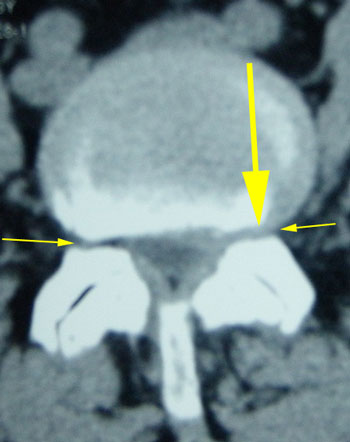

A 64-year-old white married female, presented with a complaint of left leg pain and weakness. The symptoms persisted for three weeks after gardening and lifting a heavy paving stone. The patient rated her symptoms on a visual analog scale as seven on a scale between one (no pain) and ten (worst pain). The patient reported not having these or similar symptoms in the past.

CT was ordered and shown Spinal Canal Stenosis at L4 5, and a left-sided disc prolapse with impingement of the left L4 root.

SLR=60 on the left reduced reflex and foot drop

The patient was treated with Non-Surgical Spinal Decompression and responded well to treatment. She was released asymptomatic at the end of treatment regaining complete strength in her foot.